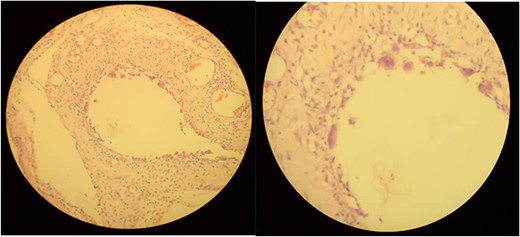

Microscopic examination shows variable-sized cystic spaces lined by thin fibrous stroma with focal multinucleated macrophages surrounding the space and intervening fibrous stroma with congested blood vessels and neutrophil mixed inflammatory cells.